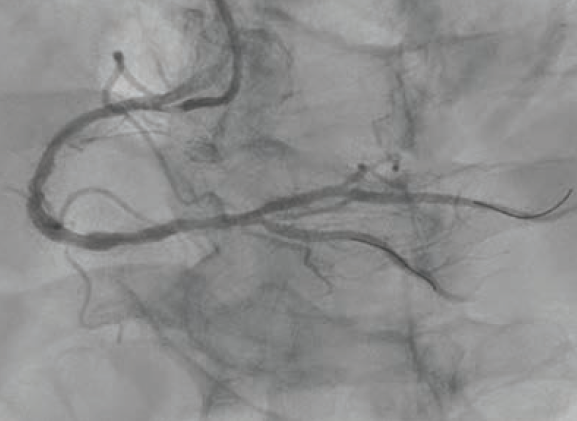

A 6 French AL 0.75 guide catheter was used to engage the ostium of the RCA. A Runthrough® NS Extra Floppy coronary guidewire was placed in the right posterolateral branch, while a Runthrough NS Izanai™ wire coronary guidewire was advanced to the right posterior descending artery (RPDA) as a buddy wire. Initial predilation was attempted with a 2.5 mm x 15 mm NC Euphora™ balloon (Medtronic), but this would not pass the lesion. A 6 French LiquID® guide catheter extension (Seigla Medical) was introduced for additional guide support. Despite this, the 2.5 mm NC Euphora™ was still unable to reach the area of interest without pushing out the guide. A 2.5 mm x 15 mm NC Takeru™ PTCA balloon dilation catheter was used instead, and was successfully brought to the diseased segment and inflated to high pressure. The rest of the proximal and mid vessel was also pre-dilated with the same balloon. We still could not bring the 6 French Opticross™ HD IVUS catheter (Boston Scientific) to the desired area due to the calcific nodule. Therefore, a 2.5 mm x 12 mm C2+ IVL balloon (Shockwave Medical) was used to deliver 70 total pulses to the mid RCA. This was followed by a 3.0 mm x 12 mm C2+ IVL balloon, with which 90 pulses were administered at 4-6 atmospheres (atm) each. Angiography showed reasonable luminal gain (Figure 2).